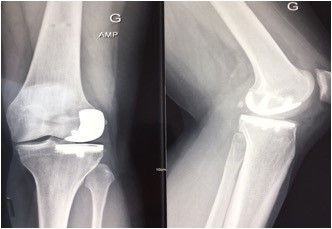

a. Bicruciate-retaining arthroplasty

There is a long history of bicruciate-retaining total knee replacements (Fig. 22) with promising long-term results but a reputation as a technically demanding procedure. Robotics have provided considerable assistance for surgeons undertaking this type of arthroplasty, which requires a meticulous understanding of the difference in joint space between the lateral and medial compartments, as well as highly accurate bone preparation (Fig. 23). Protecting the tibial spines is also much easier when using a bur guided by a robotic handpiece.